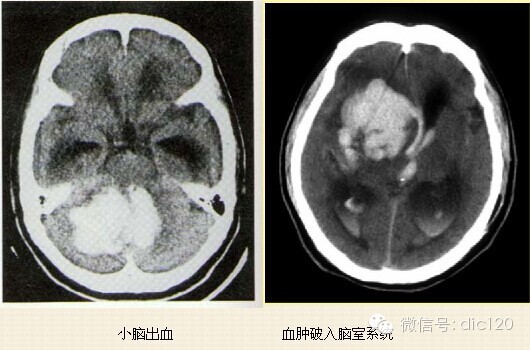

诊断:高血压性脑出血多见于50岁以上的高血压患者,常因情绪激动、过度脑力、体力劳动或其他因素引起血压急剧升高,导致已病变的脑血管微小动脉瘤破裂出血,病人突然出现意识障碍和头痛、偏瘫等。及时行头部CT以鉴别是脑出血或脑梗死,出血可破入脑室或合并脑积水。